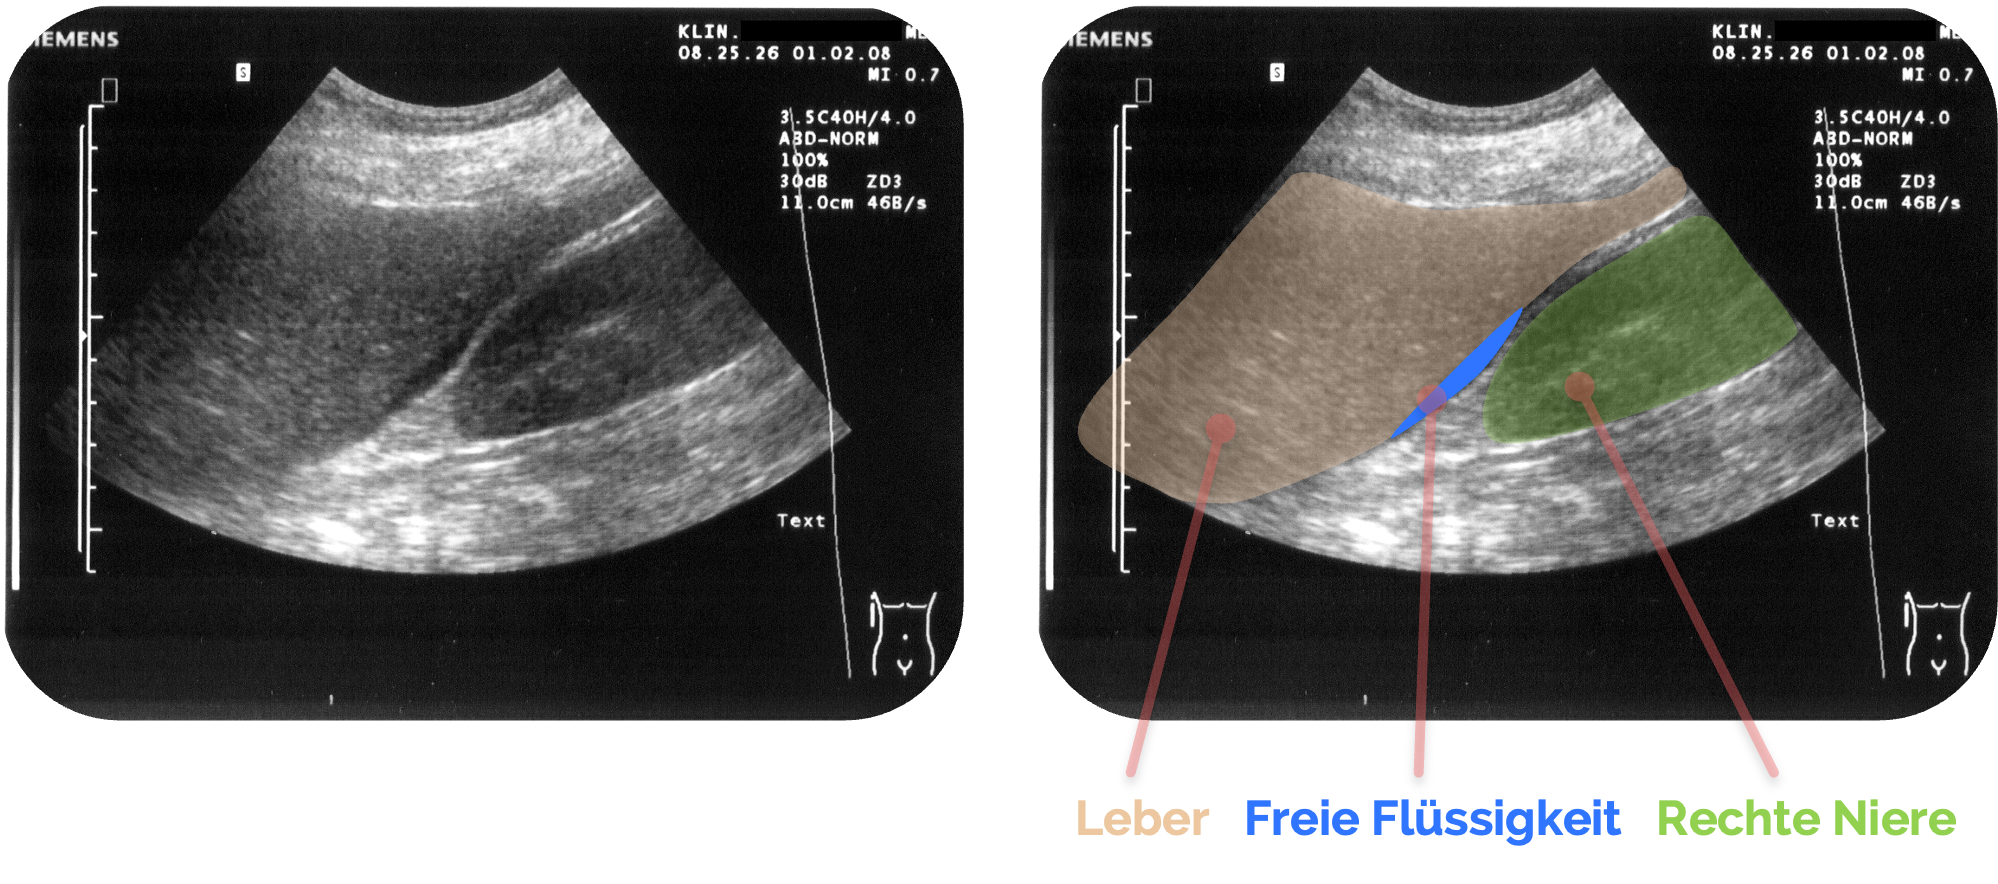

Schritt 2: Orientierung - Anatomische Grundstrukturen finden

- Leber

erscheint homogen echoreich im oberen Bildbereich - Darunter liegt die rechte Niere, typischerweise etwas kaudaler und dorsal

- Dazwischen befindet sich der Morrison-Pouch (Recessus hepatorenalis) (siehe Pfeil)

- Rechts davon häufig das Zwerchfell

MorisonNoText.png, I, Drahreg01, CC BY-SA 3.0, http://creativecommons.org/licenses/by-sa/3.0/, via Wikimedia Commons. Es wurden die Markierung und die Beschriftungen ergänzt.

Freie Flüssigkeit stellt sich als anechore (schwarze), scharf begrenzte Flüssigkeitssichel zwischen Leber

Freie Flüssigkeit zeigt sich typischerweise als echofreier oder echoarmer Spalt, der sich keilförmig in den sonst eng anliegenden Raum einschiebt.